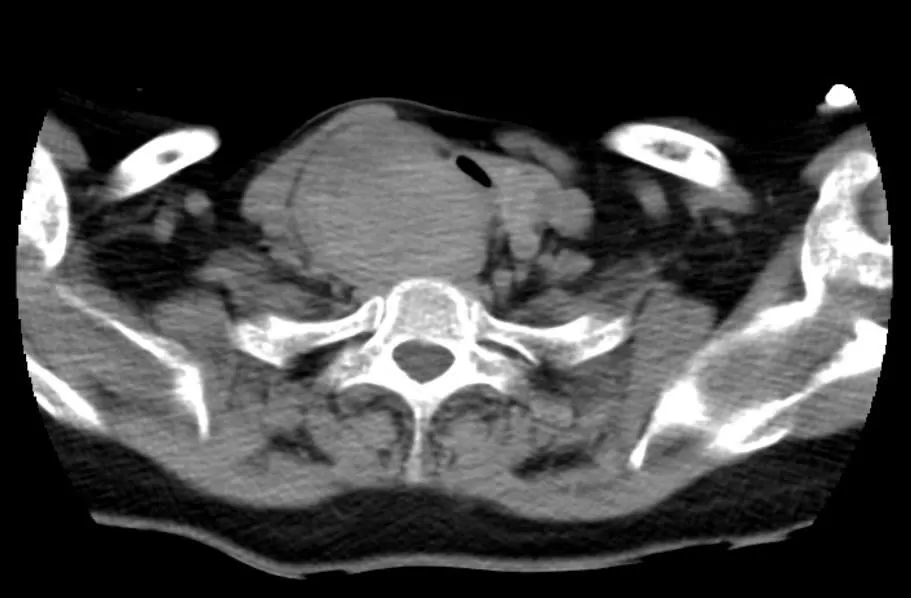

Các kết quả chụp cắt lớp cho thấy khối u chèn ép nghiêm trọng lên khí quản và thực quản, khiến đường thở chỉ còn khoảng hẹp nhất 2mm trên đoạn dài 20mm kéo dài từ góc hàm bên phải tới trung thất trên gây biến dạng giải phẫu. Đáng chú ý, khí quản của bệnh nhân bị đẩy lệch trái 2 cm, xẹp, dễ co thắt, khiến việc tiếp cận và bóc tách gặp nhiều rủi ro. Khối u tăng sinh mạch rất mạnh, nguy cơ chảy máu trong và sau phẫu thuật cao.

Hình ảnh khối u chèn ép khí quản và thực quản

Hình ảnh đường thở khoảng hẹp nhất 2mm trên đoạn dài 20mm